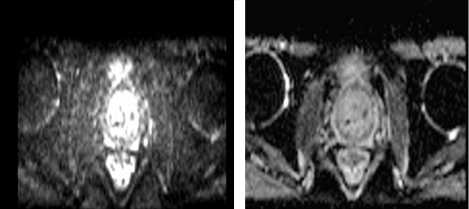

MRI:中央带、移行带、外周带异常信号,突破包膜、累及尿道;PI-RADS评分5分。

图1 2024年11月23日MRI检查

2025年6月14日,前列腺MRI示:与前片(2024年11月23日)对比前列腺体积缩小,形态欠规则,信号不均匀,治疗后改变。前列腺移行带多发结节状长T2信号影,较前减少,缩小,T2WI评分PI-RADS 2,考虑增生结节。双侧精囊腺炎,较前相仿。原膀胱导尿管留置,现已取出。膀胱炎可能,较前改善。盆腔少量积液,较前基本吸收。骶管囊肿,较前相仿。

图4 2025年6月14日MRI检查